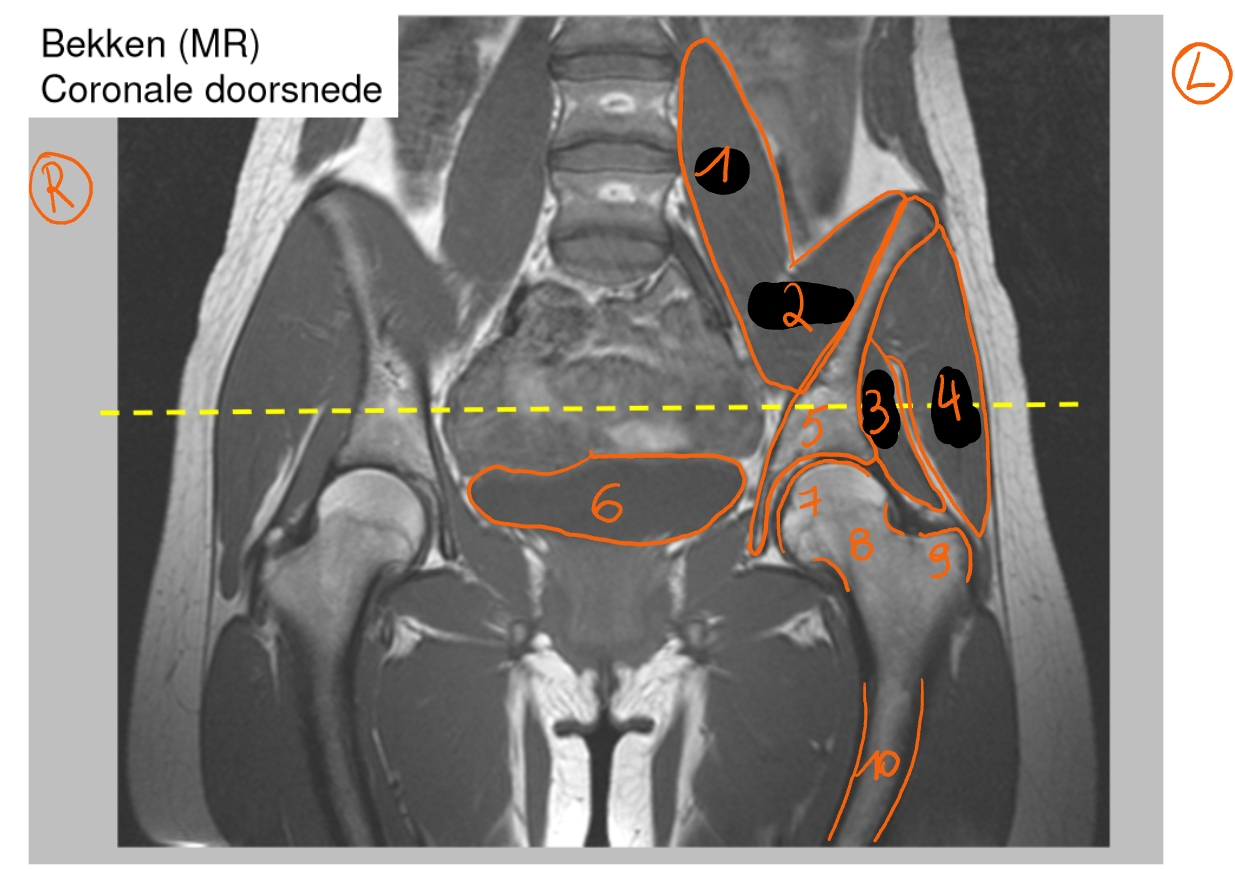

m. psoas

m. iliopsoas

m. psoas + m. iliacus = m. iliopsoas

m. gluteus minimus

m. gluteus medius

os ilium

blaas

caput femoris

collum femoris

trochanter major

diafyse

→ bekken: coronale doorsnede

→ MRI: T1-beeld